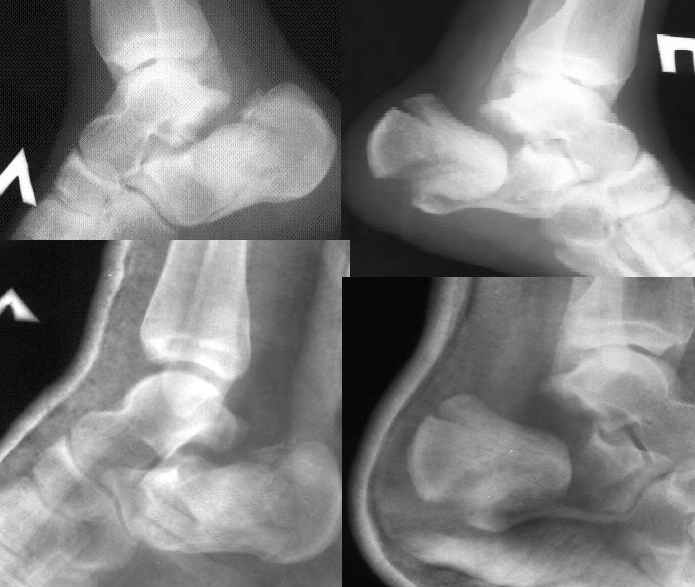

Уважаеемый коллега.Слева ситуация достаточно не сложная.Суставной фрагмент вклинился в тело.Необходимо наружным доступом освободить отломки,поднять суставной фрагмент и фиксировать пяточной пластиной LCP.

Справа ситуация сложнее так как имеется помимо перелома имеется вывих тела пяточной костиПоэтому даже если удастся достигнуть хорошей репозиции необходимо сделать первичный подтаранный артродез.Иначе кость не будет держать в своём ложе.Но пластина нужна обязательно чтобы восстановить форму пятки.С уважением Дрягин

Если нет опыта применения в подобных случаях накостного остеосинтеза, весьма велик риск осложнений: в первую очередь нероза кожи в обл. операционной раны со всеми вытекающими. Альтернативой может служить чрескостный остеосинтез.

Альтернатива-КДО. Базовый аппарат из 2х колец в н\3 голени, 2 стержня Шанца по бокам от пяточного бугра до линии перелома, затем используя стержни как рычаги закрытая репозиция и стержни соединяются с базовым аппаратом. На стопе ещё полукольцо и спица ч\з основания плюсневых костей. При успешной репозиции стержни вкручиваются дальше во второй отломок, повышая тем самым жёсткость фиксации.